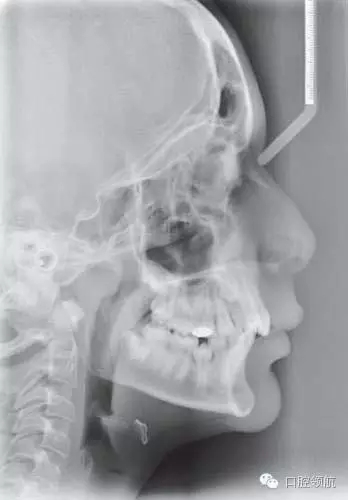

圖2.43顯示的是該患者的頭側(cè)位片,請(qǐng)總結(jié)其錯(cuò)牙合情況

● 13歲男性患者,I類關(guān)系,輕度骨性II類,均面型。

● 骨性因素:輕度骨性II類畸形,下頜后縮,并導(dǎo)致尖牙1/2牙尖的II類關(guān)系。

評(píng)價(jià)軟組織側(cè)貌及其和治療方案的關(guān)系

軟組織側(cè)貌豐滿。鼻唇角在90°~110°之間,上唇略靠前,唇紅飽滿。上下唇厚且健康。頦唇溝相對(duì)較深??偟膩?lái)說(shuō),軟組織側(cè)貌是可以接受的,并且在拔牙內(nèi)收后仍不失美觀。